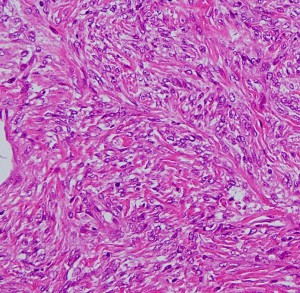

画像と病理所見2

この例は,膠原線維 collagenous tissueのなかに紡錘形の核を有する細胞 spindle cell が見られます。核の大小不同は見られますが,上の例よりはグレードが低いと捉えられます。しかし,この例のように一見グレードが低いと思われる例でも髄液播種や全身転移を生じることがあります。